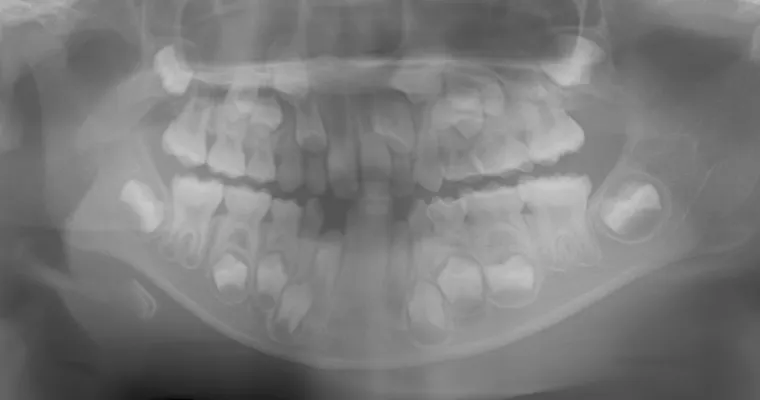

治療前 パノラマレントゲン

治療前 セファロレントゲン

| 主訴 | 歯並びが悪い 乳歯と永久歯が重なっている 歯がまっすぐはえてこない |

|---|---|

| 治療期間 | 6-7ヶ月 |

| 治療費 | 440,000円(税込) ※調整、器具、治療後にお渡しするEFLine(矯正後の後戻りを防ぐ器具)も全て込みでの金額となっております。 |

| 治療内容 | 拡大床矯正 EF Lineで筋機能療法 |